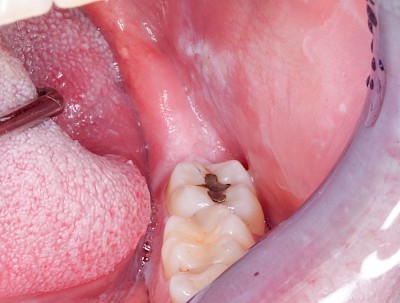

Metalltätowierung

Häufig zu beobachten sind einzelne dunkle Flecken im Nahbereich der Zähne. Häufig handelt es sich dabei um Amalgam- oder Metall-Tätowierungen. Bei zahnärztlichen Behandlungen kann es zur "Versprengung" von Metall-Anteilen von Füllungen oder Kronen kommen. Diese lagern sich dann reizlos in die Schleimhaut ein.

Beispiele 10 Bilder